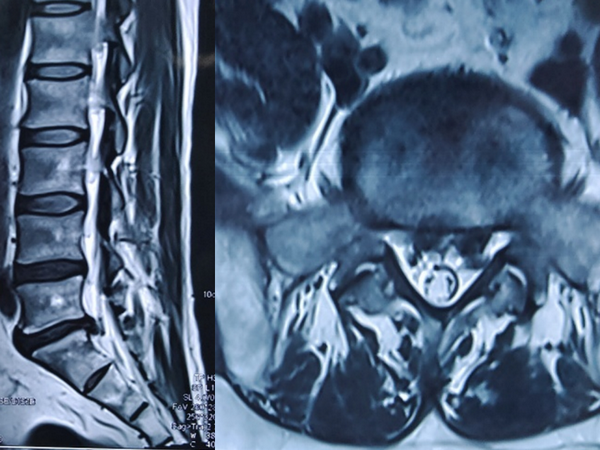

术前检查

检查提示腰5/骶1椎间盘向左后脱出,脊髓神经受压明显。骨科一病区徐明杰主任、王三木医师团队认真诊查病人,认为患者存在腰5/骶1椎间盘向左后脱出并椎管狭窄,保守治疗差,需要手术扩大狭窄的椎管并摘除突出的腰椎间组织解除神经受压,适合采用UBE技术为患者进行手术治疗。术前,徐明杰主任团队制定了严密的手术治疗方案,并与患者及家属充分、细致沟通。